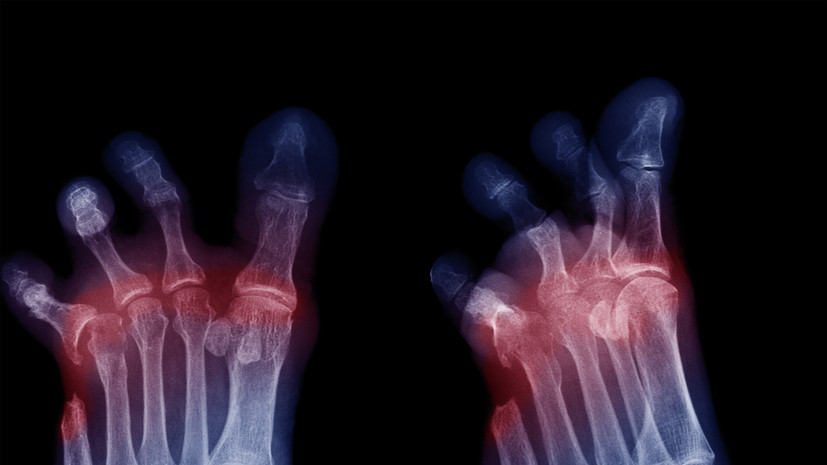

Врач заявил о необходимости применения инновационных методов лечения ишемии ног

В беседе с газетой «Известия» эксперт отметил, что использование эндоваскулярных технологий позволит дать пациентам шанс сохранить ноги при заболеваниях диабетом и атеросклерозом артерий нижних конечностей.